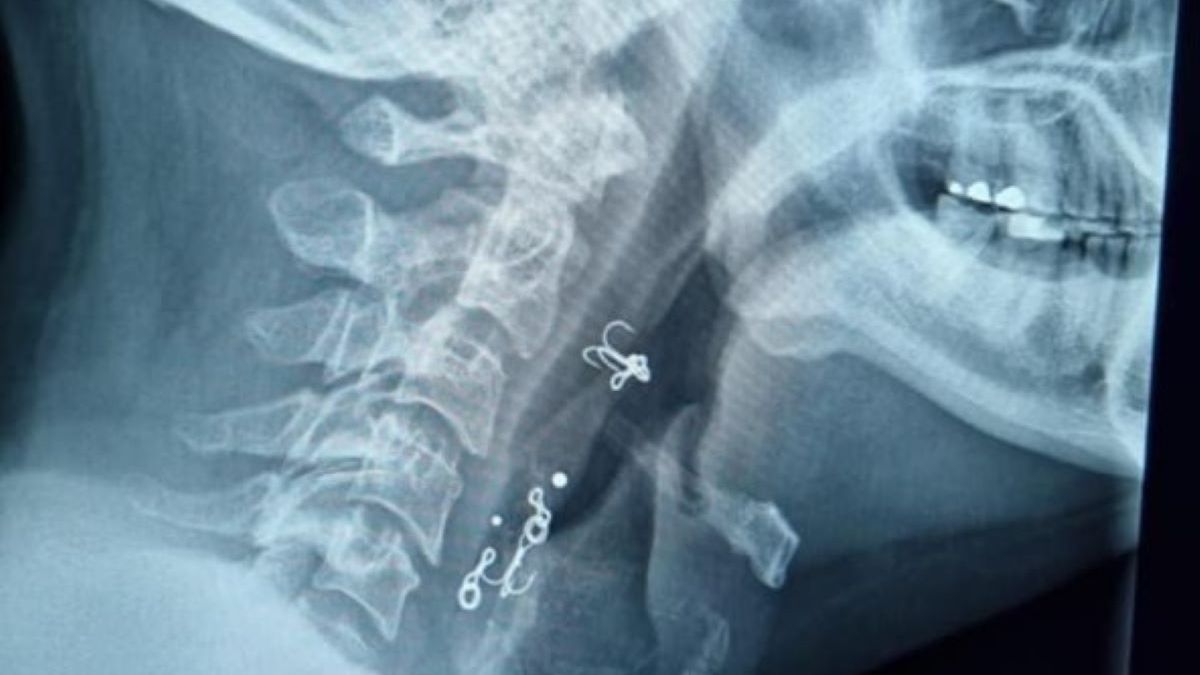

Szokujące odkrycie podczas prześwietlenia. Na zdjęciu rentgenowskim lekarz wykrył maleńkie haczyki wędkarskie… w gardle rybaka. Jak się tam dostały?

Dr David Green, profesor nadzwyczajny Gold Coast Health w Australii, wykonał badanie w tym tygodniu. Na obrazie wyraźnie widać metalowe haczyki na ryby, które utknęły w gardle pacjenta.